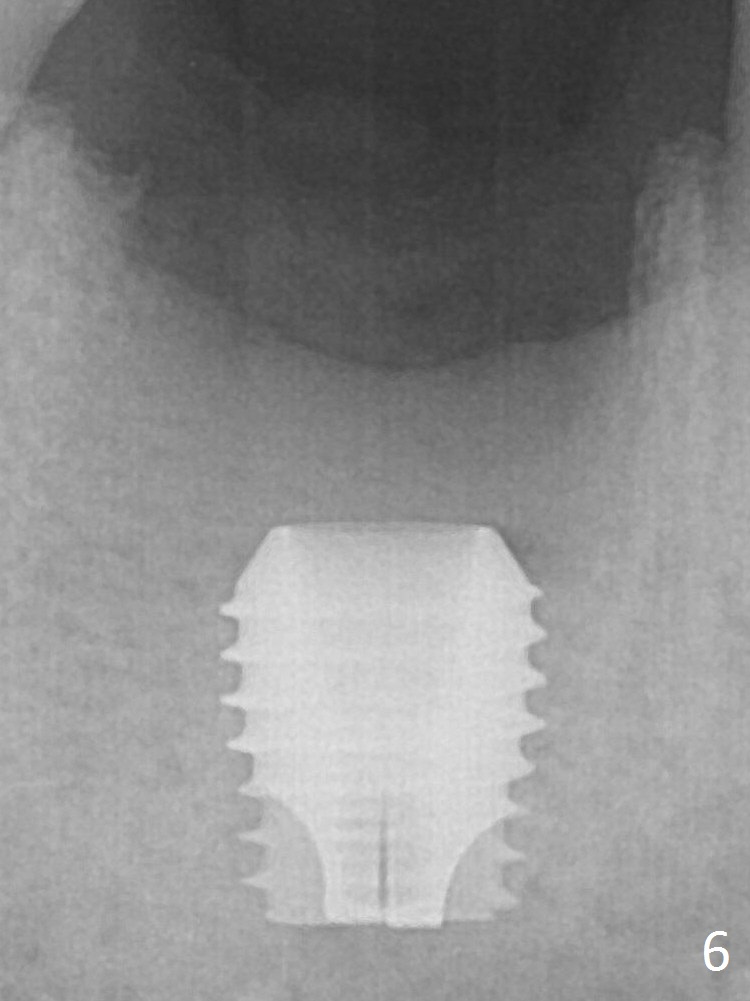

A 5.9x6 mm SM implant is placed with >50 Ncm following Septocaine infiltration (Fig.6).